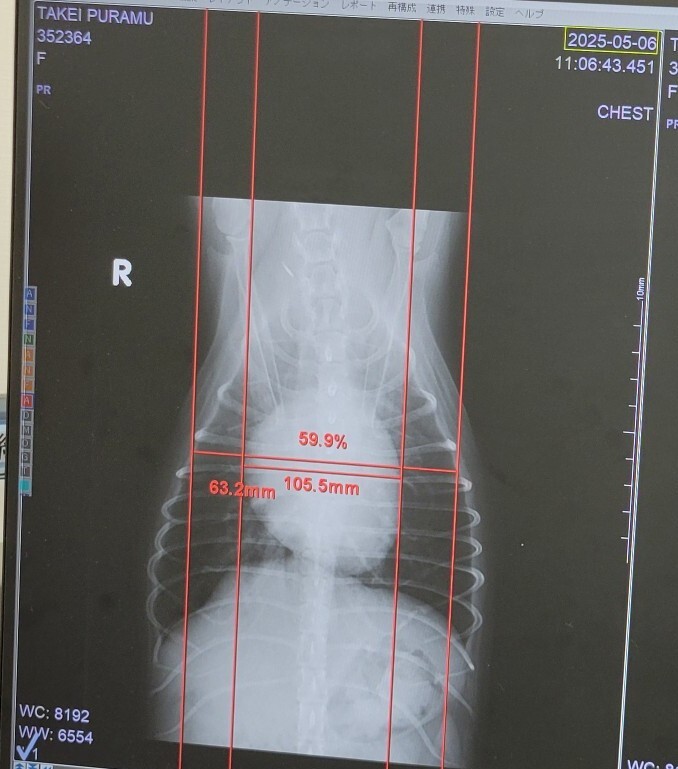

左が入院時・右が一週間後。心臓の周りのもやのようなものが肺水腫とのこと。一週間後には治まり、心臓の大きさも小さくなりました。

その後、失神を起こした後の状況。幸い、この時は肺水腫は再発していないようですが、退院時より心臓が少し大きくなっています。

病院では僧帽弁閉鎖不全症のステージC・三尖弁閉鎖不全症・不整脈という重度な状態と診断され、その後しばらく自宅で一日2回の薬で様子を見ていましたが、少しずつ咳が出始め、6月2日に再度失神し、肺水腫も再発しており2度目の入院となりました。(6月5日退院)